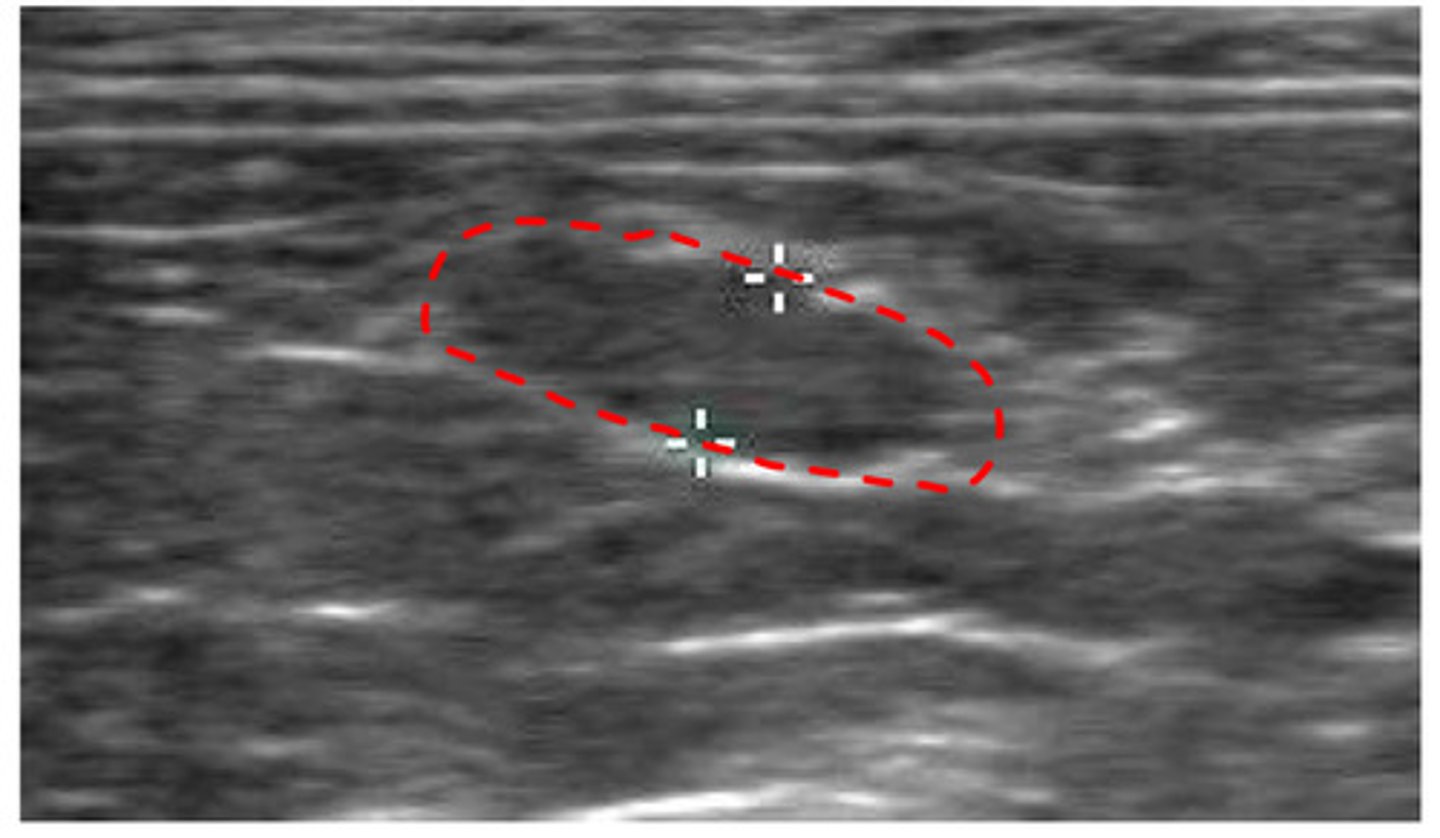

ID structure

lymph node

what structure is this?

lymph node

ID structure

lymph node

ID